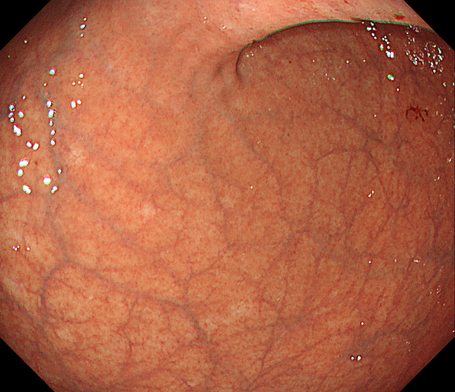

内視鏡下バルーン拡張術

消化管の狭くなっている部分に対してバルーン(風船)を用いて広げる治療になります。

主な対象疾患としては、術後吻合部狭窄や炎症性腸疾患(IBD)炎症瘢痕狭窄などの良性狭窄になります。